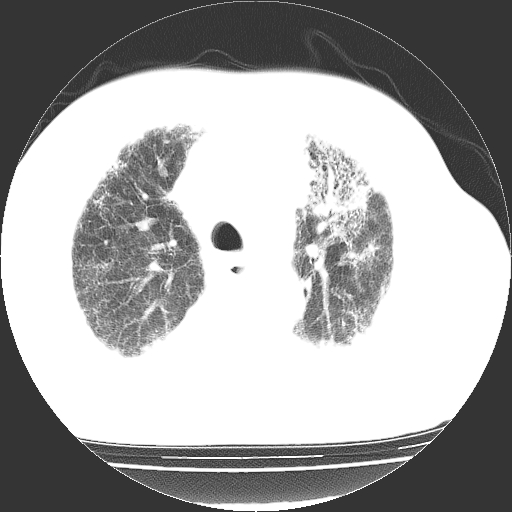

男,68岁,咳嗽、胸闷、发烧三天,查体:双肺散在湿罗音。

依据:1、两肺广泛条索状、网格状、蜂窝状改变。

双肺多发条索状、网格状及小灶状密度增高影。考虑慢支合并感染.间质纤维化,双侧少量胸腔积液

两肺广泛条索状、网格状、蜂窝状改变。肺间质纤维化,肺心病,双侧胸腔积液